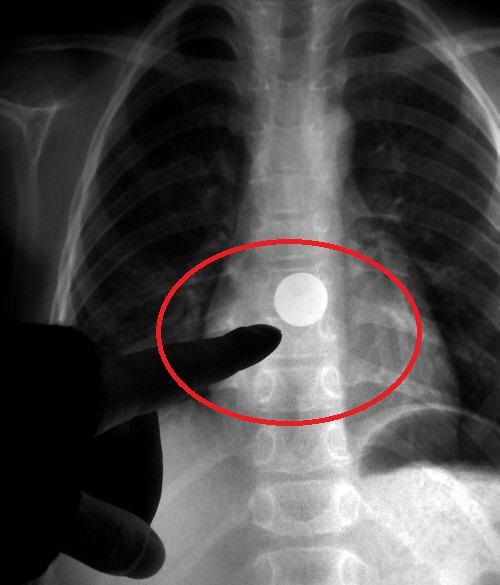

大悟3岁幼儿吞入一角硬币,辗转赴武汉取出

经过诊断,发现孩子的食道内有一个圆形金属异物,疑似硬币.

科室采用间接喉镜观察咽喉部未见异物,又通过x光片检查,提示异物在